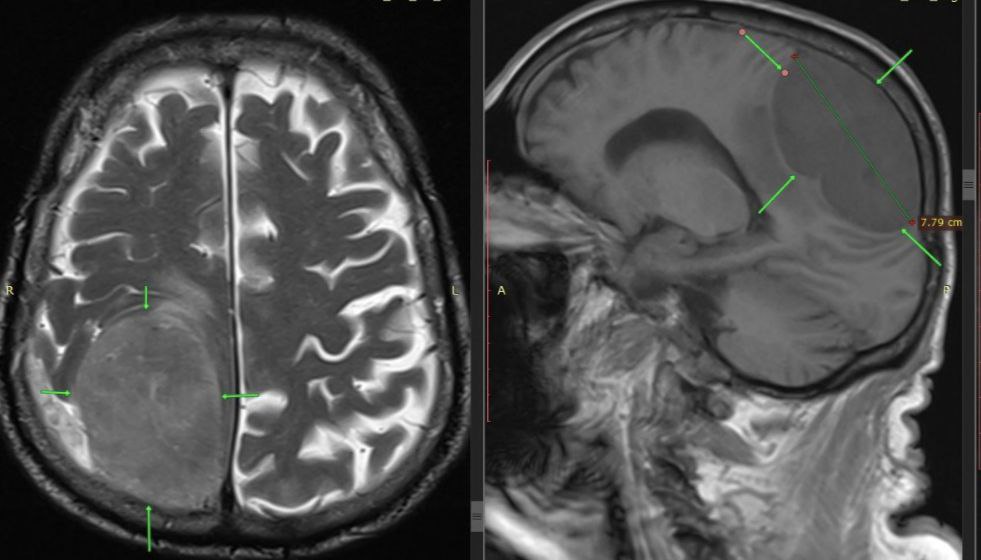

В ГКБ Пятигорска поступил 85-летний пациент с парализованной левой ногой и половиной тела. Первоначально врачи предположили инсульт, однако срочное обследование выявило огромную опухоль размером 8×7 см в правой теменно-затылочной области мозга, отвечающей за движение левой стороны.

Нейрохирурги провели костно-пластическую трепанацию и полностью удалили новообразование.

После вмешательства пациент быстро пошел на поправку, восстановил движения в левой половине тела. Гистологическое исследование подтвердило доброкачественный характер опухоли.